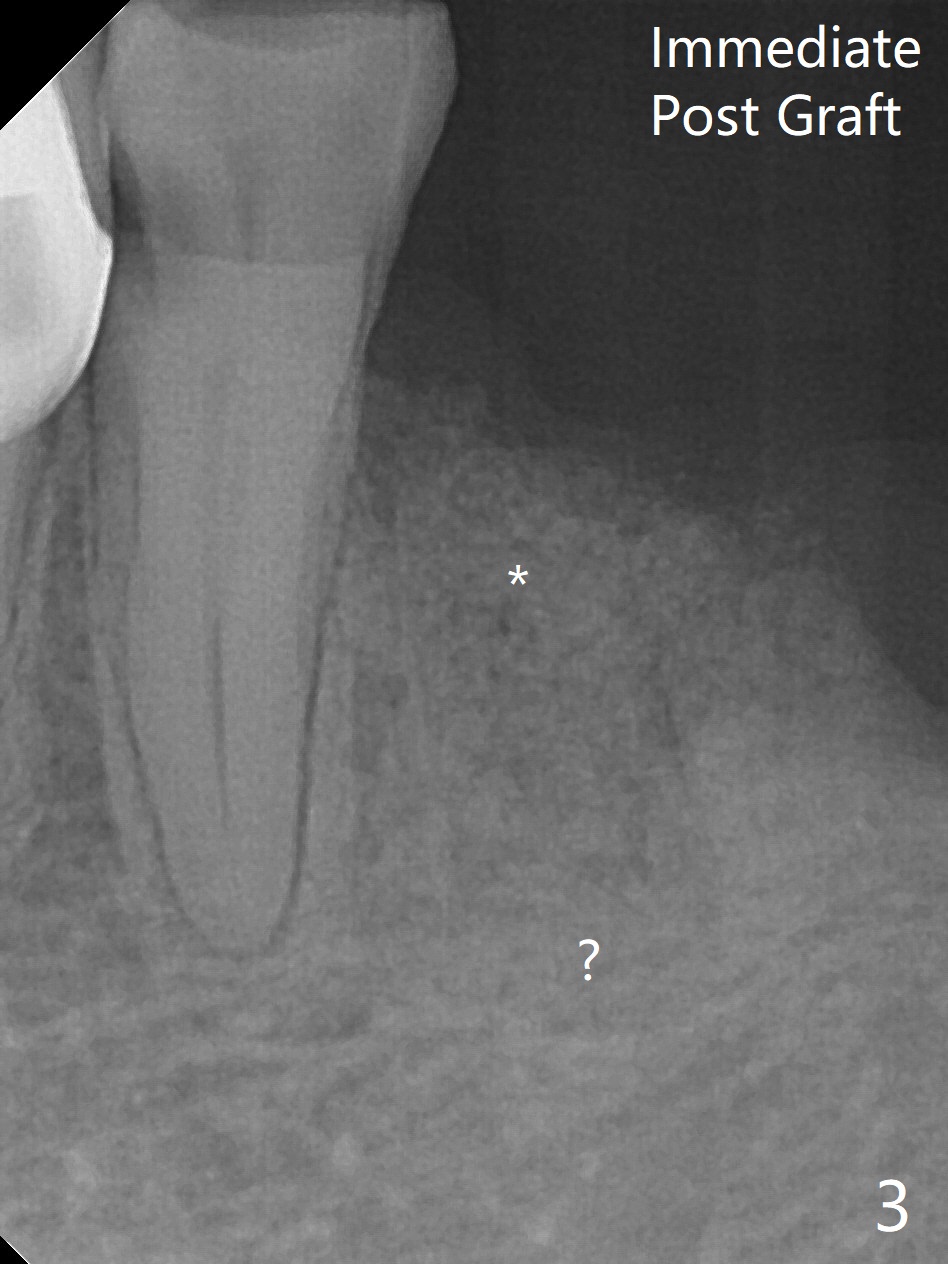

A 85-year-old woman has had poor dentition (Fig.1). She requests extraction of the tooth #21 with crown fracture (Fig.2 <) and PARL (*). Although the buccal plate is low, Vanilla/Osteogen mixture is used for socket preservation (Fig.3 *), while BioXclude is used to cover the socket opening. Three to four 5-0 PGA sutures appear to be able to close the socket. It is expected that the membrane with several growth factors facilitates wound healing. It seems that the bottom of the socket is not fully packed with the bone graft (Fig.3 ?). Bone condenser should have been utilized. The socket appears to heal (due to BioXclude?) with minor buccal plate collapse 1 week postop (Fig.4). Titanium membrane should have been used.